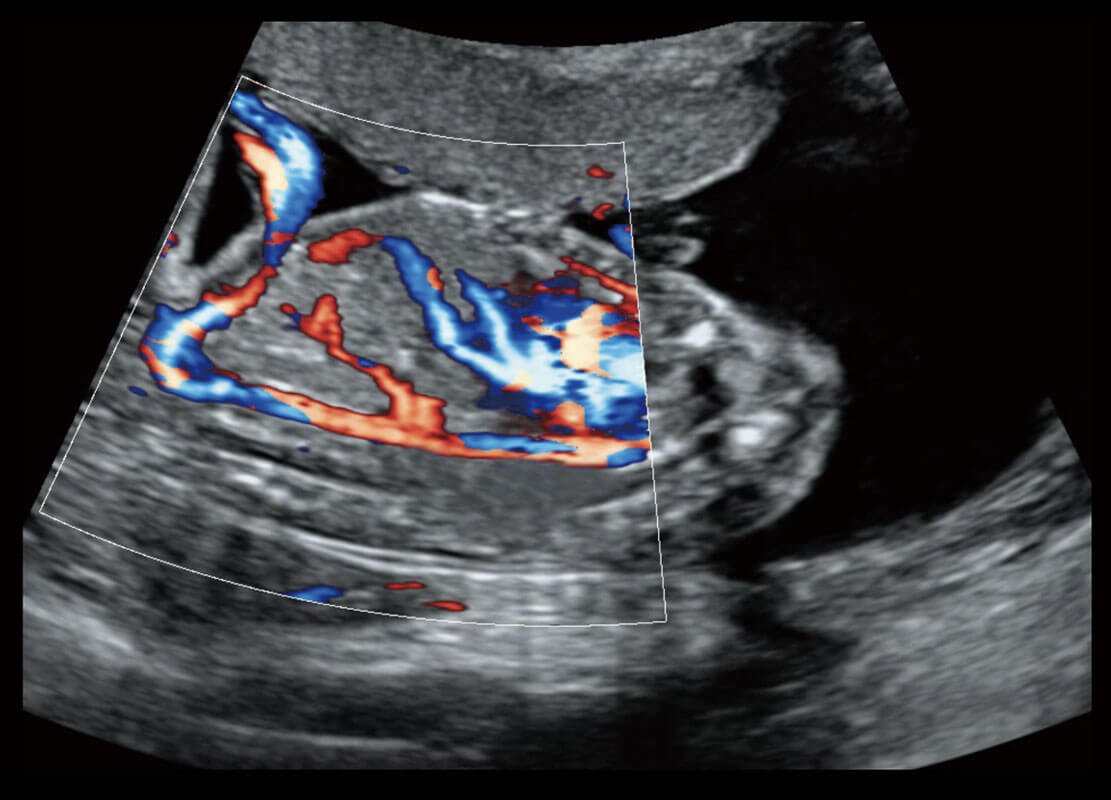

P60优异的图像质量搭载专科探头,在妇科基础疾病的诊断、卵泡生长的监测、输卵管通畅情况的判别等方面为您提供生殖应用方案。

P60搭载一系列胎儿心脏成像技术,实现精细的胎儿心脏评估。

四腔心血流